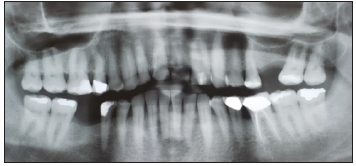

Radiograph and intraoral examinations reveal worn-down teeth [#s 07, 08 and 09] (Figures 1-5) as well as tooth gemination [# 10] (Figures 1-7). The evaluation of periapical radiographs taken of teeth [#s 07, 08, 09, and 10] presents with no evidence of periapical radiolucency. Tooth [# 08], however, shows significant internal root resorption to the mid-way and calcified the apical half of the root to the apex. Tooth [# 09] also shows a significant external/internal root resorption which is more evident on the distal aspect of the tooth, (Figure 7). Both merged segments of geminated tooth [#10] (Figure 6), shows almost completely calcified root canals to the apex. This calcification is also evident in tooth [# 07] (Figure 7).

Figure 1: Panoramic radiograph reveals no reduction in maxillary arch dentition (Counted all 16 teeth including the extracted # 14 and geminated tooth # 10, as a single tooth).